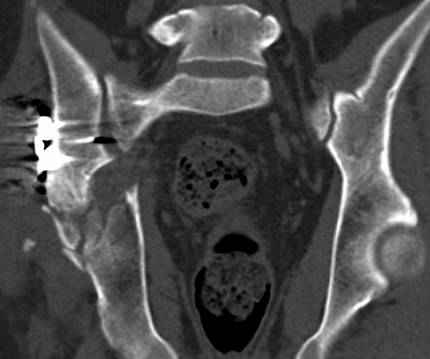

Интересно было бы посмотреть рентгенограммы до операции. У меня впечатление, что я не все вижу, что тут есть... Уважаемые Господа "тазисты" и "тазологи", к какому типу переломов вертлужной впадины по Летурнелю вы бы отнесли это случай?

Из переломов проходящих через крыло и/или заднюю стенку ни простой перелом "передней колонны" (явно имеется пером задней стенки, и не видно перелома седалищной или лонной), ни простой "поперечный", ни ассоциированный "Т-образный" (т.к есть перелом крыла и не видно перелома седалишной), ни ассоциированный "задняя колонна+задняя стенка", на ассоциированный "поперечный+задняя стенка", ни ассоциированный "передняя колонна+задняя гемисфера" (не видно перелома седалищной), ни ассоциированный "обе колонны" (не видно перелома лонной седалищной) не подходят под эту классификацию....

к таковым себя не причисляю, но...обычное дело для нашей страны - выкладывать 3D и не показывать стандартные проекции Judet. Дигност представляет те ракурсы, которые по-его мнению наиболее информативны, более того комп сам достраивает какие-то мелкие повреждения по 3D по своему усмотрению. По данной реконструкции можно предполагать высокий двухколонный перелом с оскольчатыми передней и задней колоннами, оскольчатую высокую переднюю колонну с задним полупоперечником или одно из перечисленных с вовлечение КПС. У меня впечатление за второй вариант, но нужно обследовать нормально - проекции, сканы.

высылаю дополнительно сканы.